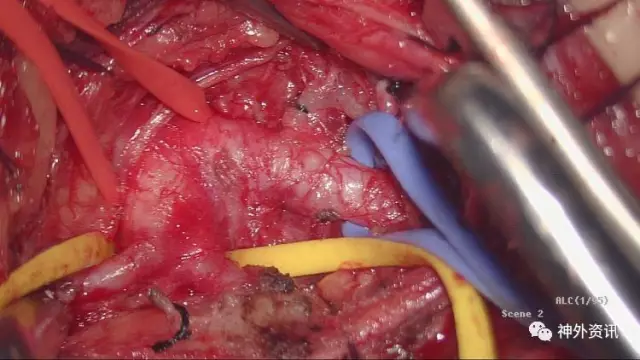

术中视野

这个是左侧椎动脉三角的解剖:由于左椎开口位置深在,前方有胸导管横过,毗邻神经血管丰富,手术操作较右椎A开口段手术要困难一些,病人胸导管损伤、膈神经牵拉副损伤、胸膜顶损伤致气胸的风险较高,因而手术要求熟悉局部解剖,有较好的显微操作基础

赵鹏博士在做手术显露,病人服着单抗,这个层次很明晰,手术视野基本是无血手术,这样的术野你能看到每一条血管和神经,术中副损伤和意外情况会降到最低